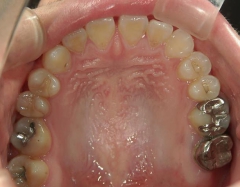

矯正歯科 治療前 急速拡大装置で上顎を広げた後、ワイヤーへ移行 非抜歯

矯正_灰色.pngno.31_7964_治療前_上 .JPG矯正_灰色.png

no.31_7964_治療前_右 .JPGno.31_7964_治療前_正面 .JPGno.31_7964_治療前_左 .JPG

矯正_灰色.pngno.31_7964_治療前_下.JPG矯正_灰色.png